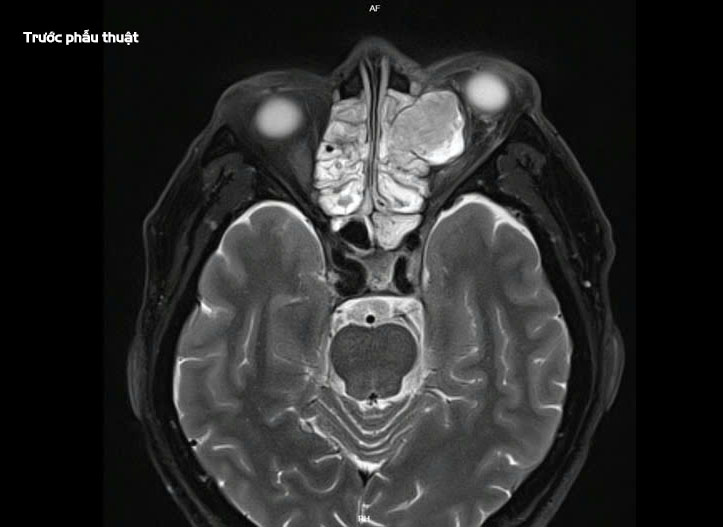

Bệnh nhân xuất hiện triệu chứng sưng đau vùng mắt trái tăng dần 7 ngày trước khi nhập viện tại Khoa Tai Mũi Họng vào ngày 10/03. Qua thăm khám chuyên khoa mắt, các bác sĩ phát hiện tình trạng hạn chế vận động nhãn cầu, mắt lồi và đau khi liếc. Kết quả chụp MRI cho thấy khối u nhầy kích thước 26x24x21mm xuất phát từ xoang sàng trước bên trái, đẩy lồi vào tổ chức phía sau hốc mắt và chèn ép cơ thẳng trong. Bệnh nhân được phẫu thuật ngày 11/03.

Chia sẻ về ca phẫu thuật, BSCKII. Dương Văn Tá cho biết: “Ca phẫu thuật này gặp nhiều khó khăn do bệnh nhân có tiền sử tăng huyết áp cao (190/110mmHg), trong khi tính chất bán cấp của ca mổ không cho phép có đủ thời gian kiểm soát huyết áp. Thêm vào đó, khối u nhầy lớn đã xâm lấn sâu vào hốc mắt, hủy hoại xương giấy và có mảnh xương đâm vào cơ thẳng trong, gây chảy máu nhiều trong quá trình phẫu thuật.”